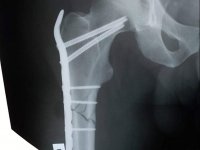

Волинські медики прооперували жінку, що впала вдома і отримала перелом стегнової кістки

Медики провели оперативне втручання - синтез стегна методом PFN.